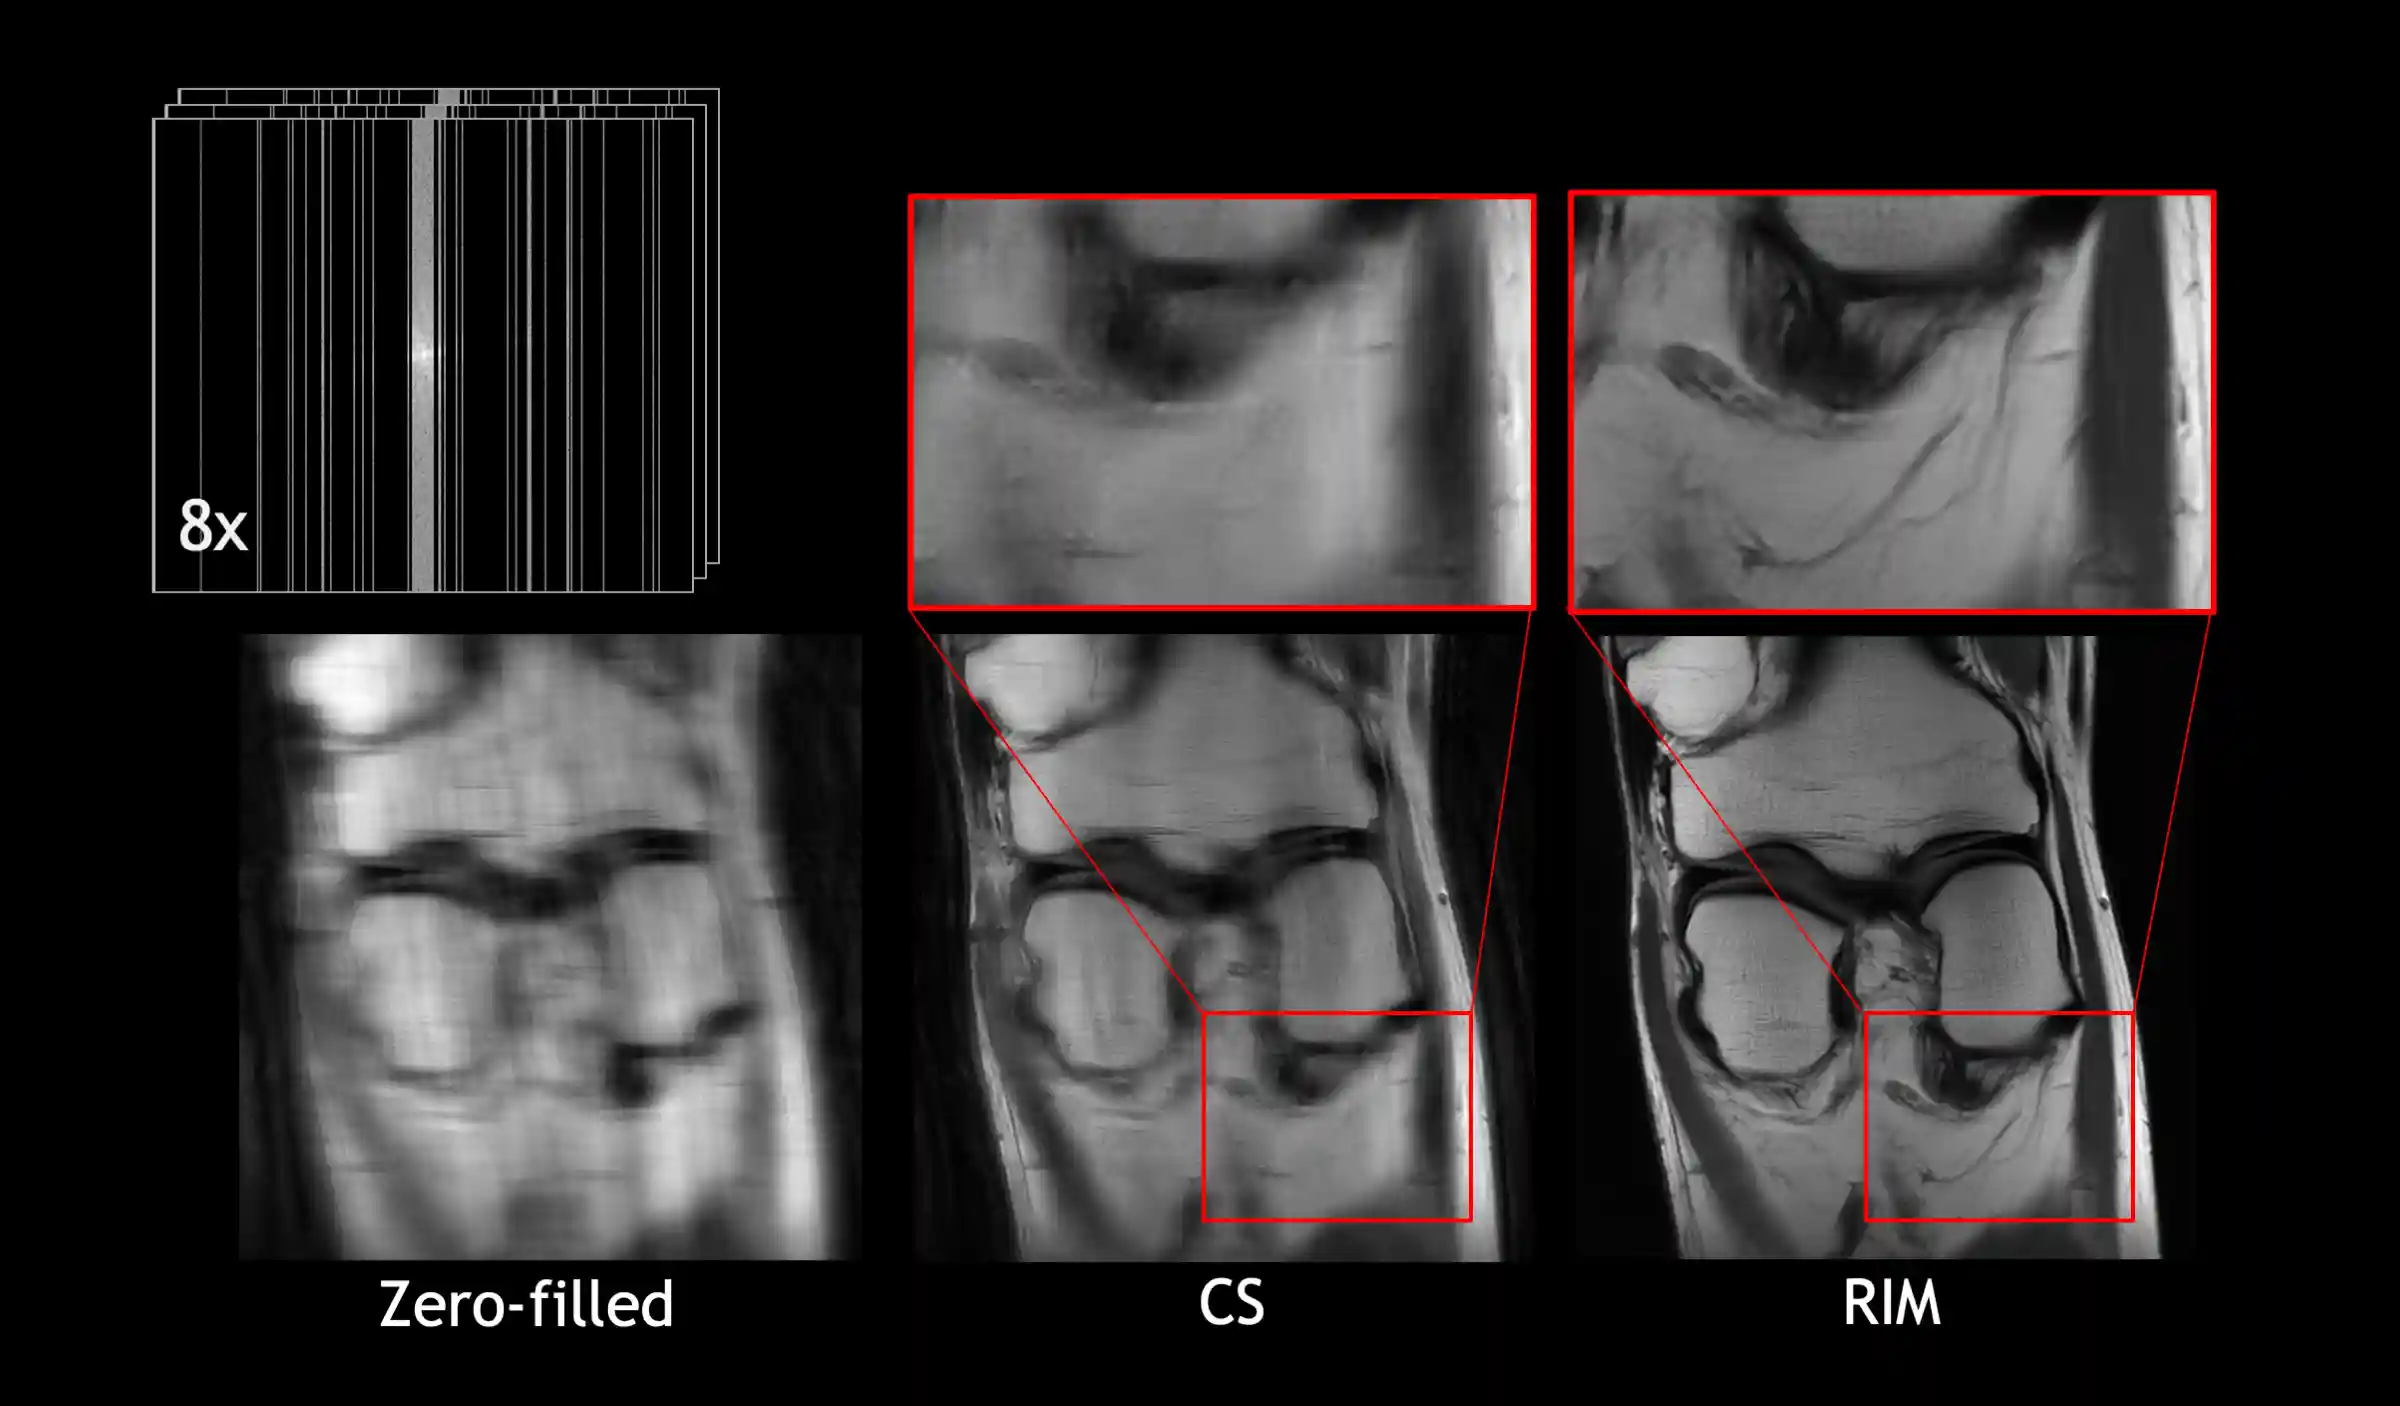

Zero-filled reconstruction, Compressed-Sensing (CS) reconstruction using the BART toolbox, Reconstruction using a RIM model trained with DIRECT